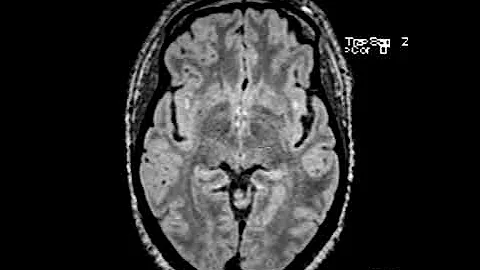

White Matter Changes On Your Brain Mri? What Should Your Mri Look Like With Migraine?

What are those white matter changes on your brain MRI, and what should your MRI look like with migraine? #migraine #headache ...